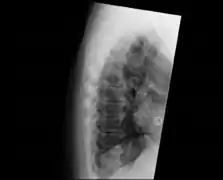

DISH in an 80 year old female, also with T11 fracture.

Diffuse idiopathic skeletal hyperostosis (DISH) is a condition characterized by abnormal calcification/bone formation (hyperostosis) of the soft tissues surrounding the joints of the spine, and also of the peripheral or appendicular skeleton.[1] In the spine, there is bone formation along the anterior longitudinal ligament and sometimes the posterior longitudinal ligament, which may lead to partial or complete fusion of adjacent vertebrae. The facet and sacroiliac joints tend to be uninvolved. The thoracic spine is the most common level involved.[2] In the peripheral skeleton, DISH manifests as a calcific enthesopathy, with pathologic bone formation at sites where ligaments and tendons attach to bone.

DISH is diagnosed by findings on x-ray studies. Radiographs of the spine will show abnormal bone formation (ossification) along the anterior spinal ligament. The disc spaces, facet and sacroiliac joints remain unaffected. Diagnosis requires confluent ossification of at least four contiguous vertebral bodies.[2] Classically, advanced disease may have "melted candle wax" appearance along the spine on radiographic studies.[13] In some cases, DISH may be manifested as ossification, or enthesis, in other parts of the skeleton.